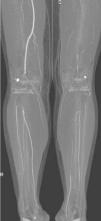

Objetivos. Evaluar la eficacia diagnóstica de la angiografía por tomografía computarizada multidetector (ATCM) en la arteriopatía de miembros inferiores (MMII), comparándola con angiografía por sustracción digital (ASD). Material y métodos. Se estudiaron 24 pacientes con arteriopatía de MMII. Se realizaron ATCM (4 detectores) y ADS realizando doble lectura entre las dos técnicas. Los territorios vasculares se dividieron para facilitar el análisis. Se calcularon sensibilidad (S), especificidad (E), prevalencia, valor predictivo positivo y negativo (VPP, VPN) y concordancia (test de Kappa). En arterias de tercera porción se estudió el rendimiento diagnóstico del ATCM realizando una curva ROC. Resultados. El estudio ATCM para la evaluación de la patología arterial mostró: una S menor en el estudio de la arteria ilíaca primitiva y arteria ilíaca interna (S: 0,65 y 0,71) con E de 0,94 y de 1; en los demás territorios vasculares obtuvimos S próximas a 1, disminuyendo algo la E. La concordancia fue muy alta (kappa entre 0,62 y 1) en todos los territorios estudiados. La ATCM mostró más longitud de vaso que la ASD. En la tercera porción el mejor rendimiento diagnóstico (ROC) se obtuvo en la lectura de vasos patológicos. Conclusión. La ATCM presentó alta fiabilidad en el estudio de la arteriopatía de MMII, con alta concordancia respecto a la ASD. En vasos tortuosos la ATCM visualiza mal las lesiones, en cambio en vasos rectos y en tercera porción el estudio con ATCM visualiza más segmentos vasculares.

Objectives. To evaluate the diagnostic efficacy of multidetector computed tomography angiography (MDCTA) in lower limb arteriopathy (LLA) by comparing it with digital subtraction angiography (DSA). Material and methods. Twenty-four patients with LLA were studied. All patients underwent MDCTA (four detectors) and DSA, with double reading between the two techniques. Vascular territories were divided to facilitate analysis. Sensitivity (S), specificity (Sp), prevalence, positive and negative predictive values (PPV, PNV), and concordance (Kappa test) were evaluated. In third-portion arteries, the diagnostic performance of MDCTA was evaluated using an ROC curve. Results. MDCTA study to evaluate arterial pathology showed: Lower sensitivity in the study of the internal iliac artery (S: 0.65 and 0.71) with Sp 0.94 and 1. In the other vascular territories, S approached 1, with a slight decrease in Sp. Concordance with DSA was very high (kappa between 0.62 and 1) in all of the territories studied. MDCTA showed greater vessel longitude than DSA. In the third portion, the best diagnostic performance (ROC) was obtained in the reading of pathological vessels. Conclusion. MDCTA was highly reliable in the study of LLA, with high concordance with DSA. In tortuous vessels, MDCTA depicted the lesions poorly; however, in straight vessels and third-portion vessels, MDCTA showed more vascular segments.